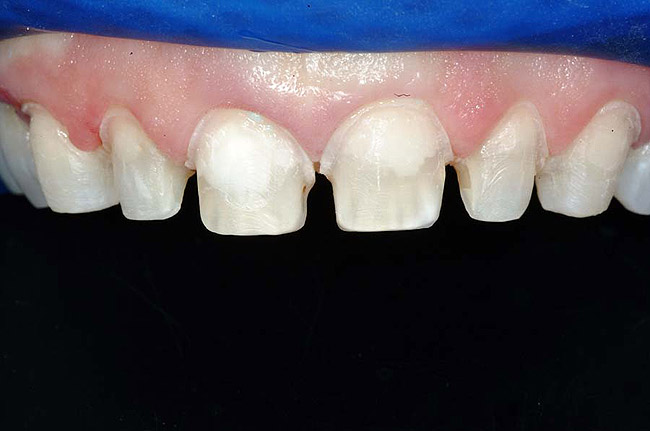

Figure 1 and Figure 2 Preoperative views of a female patient in her mid-50s who presented with a chief complaint of dissatisfaction with the appearance of her smile. Examination revealed multiple fractures, hypocalcification, shortened clinical teeth due to wear, and an asymmetrical smile line. Teeth Nos. 6 through 11 were treatment planned for porcelain laminate veneers.

In fact, scientists evaluating the long-term functionality of porcelain laminate veneers after 1 to 10 years of service observed that they had been placed for such reasons as correcting fractured and worn anterior teeth, treating surface enamel defects, and changing the appearance of intrinsically discolored dentition (Figure 2');" rem="#ip:figure1 and Figure 2">Figure 1 and Figure 2).2 These researchers found that the porcelain laminate veneer concept provided excellent esthetic and conservative restorations. In other studies, researchers observed 5-year success rates with porcelain laminate veneers,3 commenting that they offer a reliable and effective procedure for the conservative and esthetic treatment of anterior dentition.